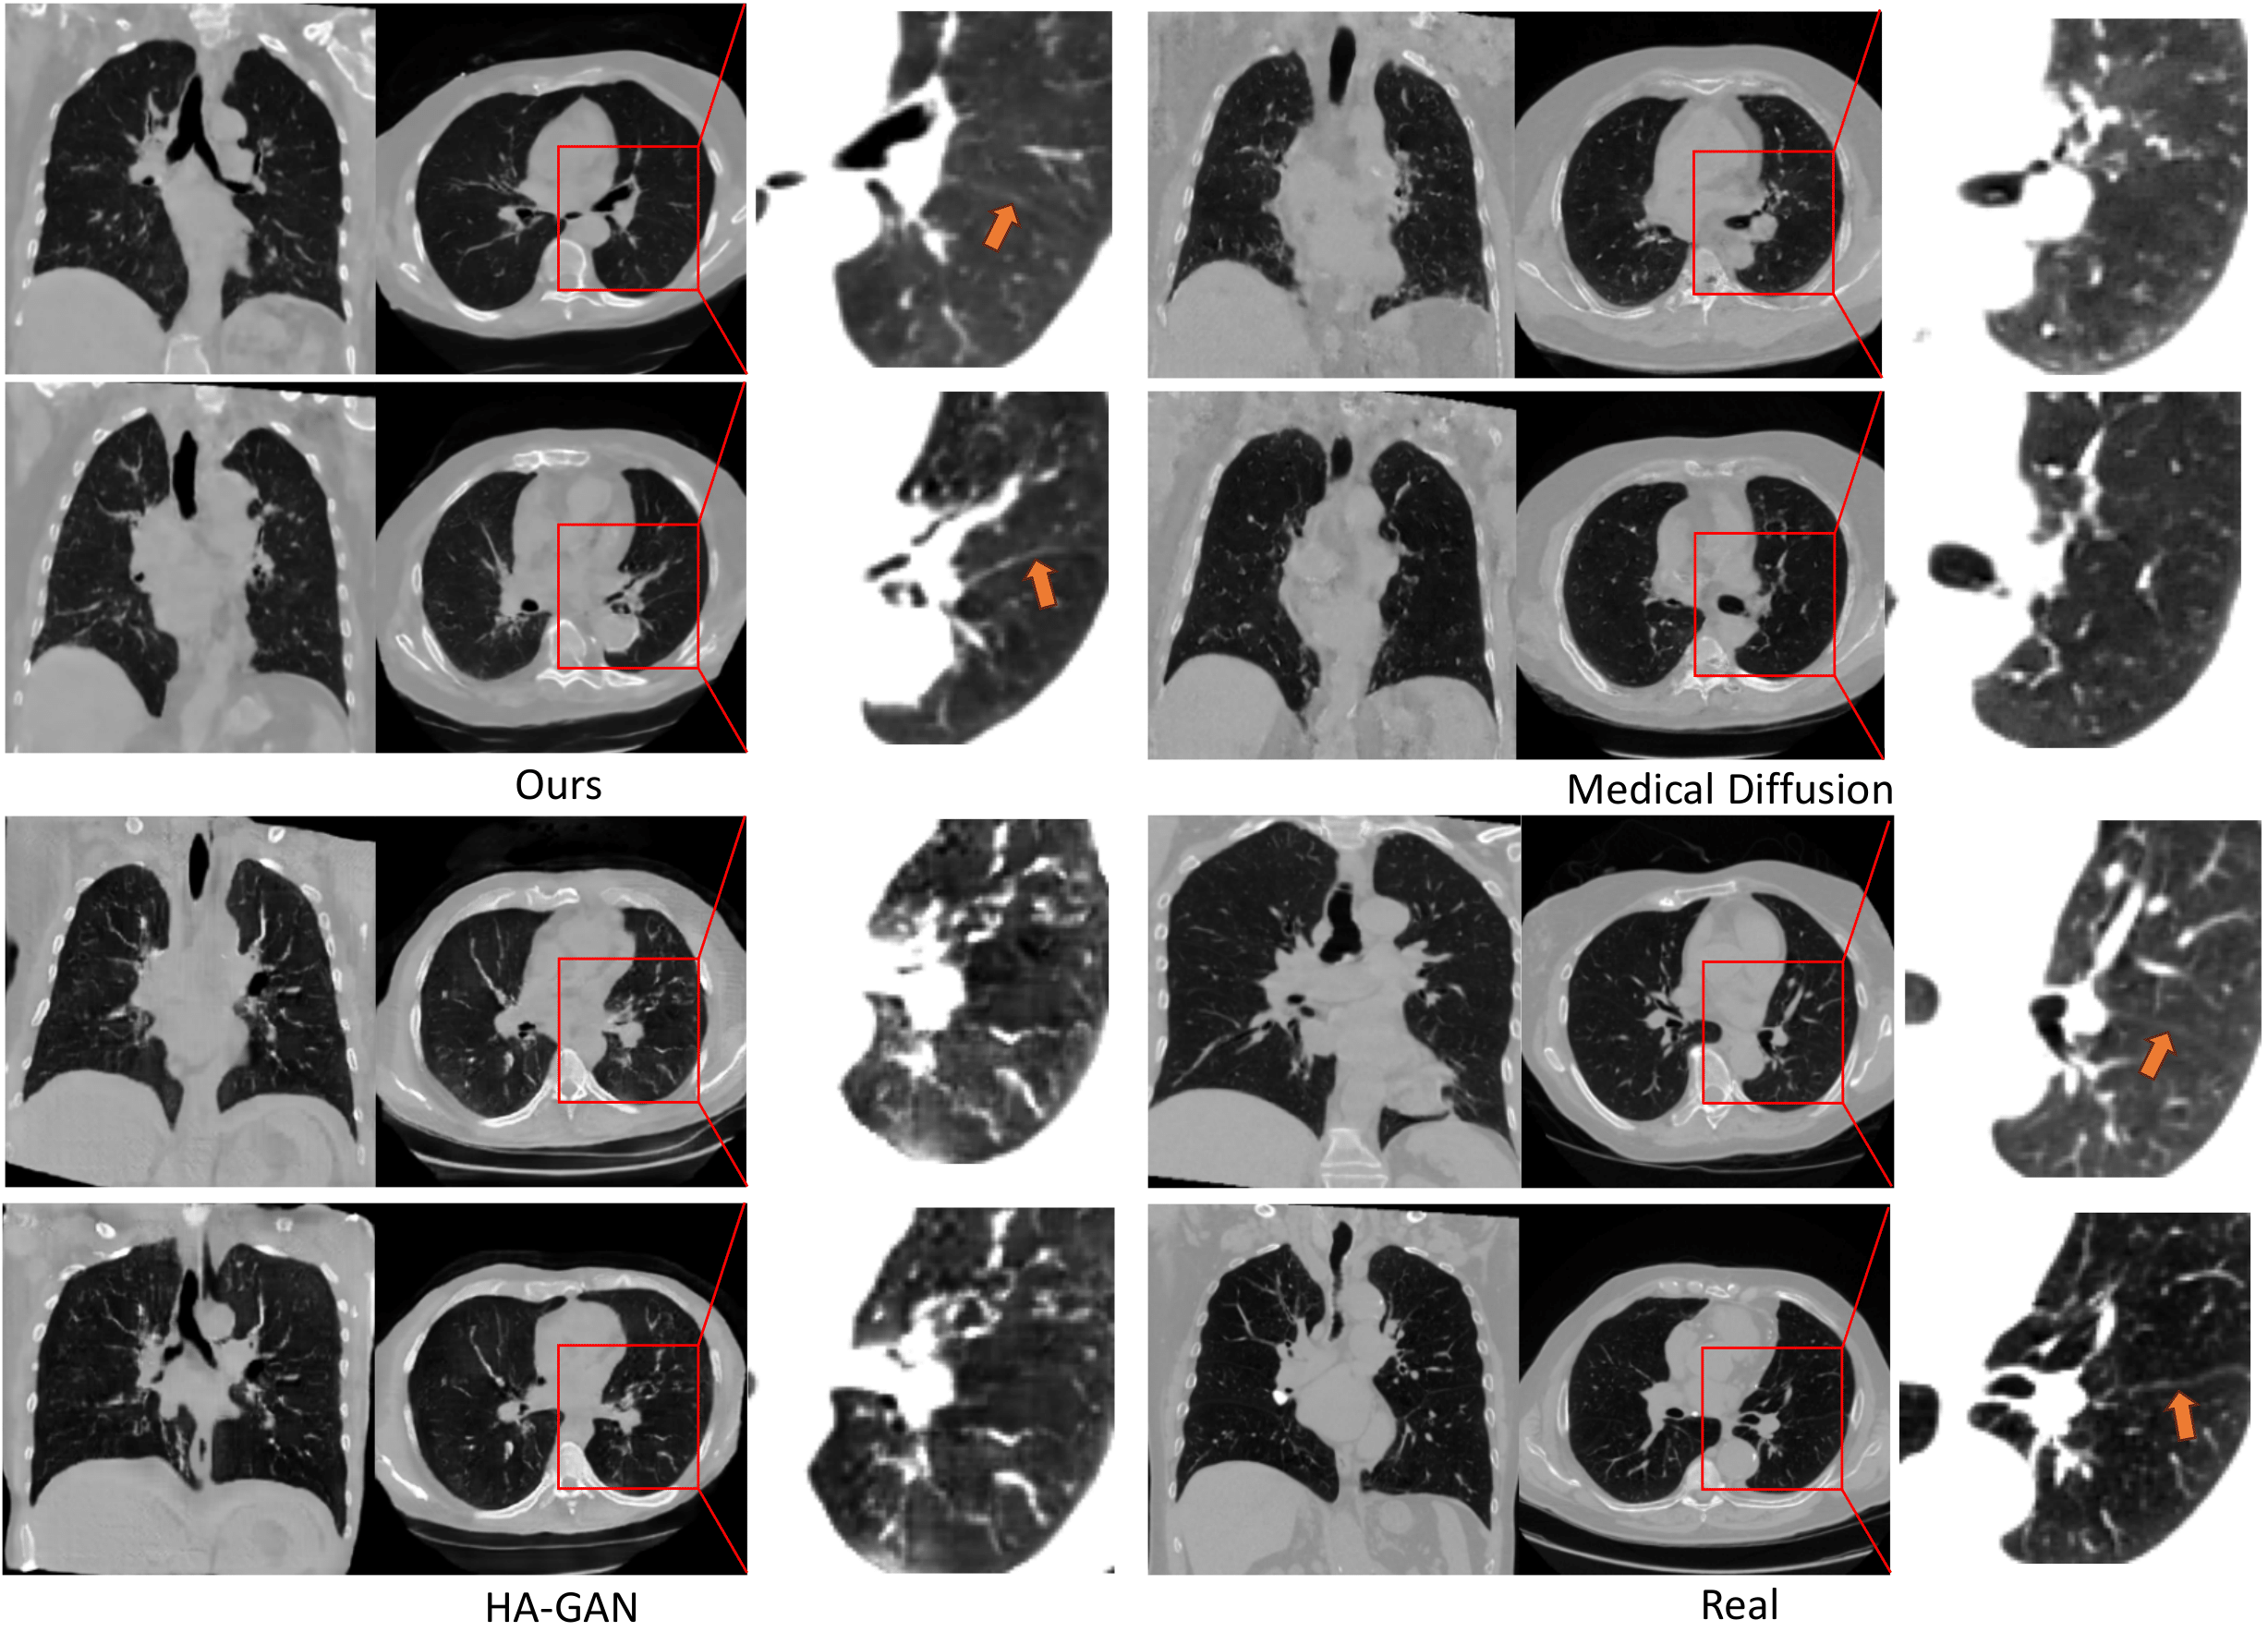

Refer to caption

Figure 3: Randomly generated images (from HA-GAN and Medical Diffusion) and the real images. The first two columns show axial and coronal slices, which use the HU range of [-1024, 600]. The last column shows the zoom-in region and uses HU range of [-1024, -250] to highlight the lung details. Our method is the only one that can preserve delicate anatomical details, including fissures, as indicated by the arrows.

Quantitative Evaluation on Anatomical Details: While metrics like FID and MMD are widely used in literature and empirically work well for natural images, they highlight the semantic-wise similarly (distance) but may ignore subtle but important anatomical details in medical images, as implied by the small (FID/MMD) gap between different methods. Their real distances, as later shows in Fig. 3, could be much bigger when taking account into the anatomical details we are focused on. Therefore, we evaluate how well the generated images can preserve the anatomical details. Specifically, we use Total Segmentor [34] to segment vessels and airways from generated images and real images, and measure the volume. The results are shown in Table. 1. We also perform statistical tests (one-tailed two-sample t-test) on the evaluation results. At the significance level of p<0.05𝑝0.05p<0.05, the results are significant for all three conditions, which further identify the effectiveness of our model on prompting generation.

5.2.2 Qualitative Evaluation

To qualitatively analyze the results, we show cases of synthetic images from current best baseline GAN [6] and diffusion model [20]. Asin Fig. 3, although synthetic images from different methods are all closed to the real ones in overall appearance, only our MedSyn consistently produces anatomically plausible CT scans upon closer inspection, showcasing its superiority.